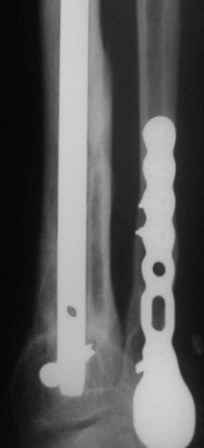

используется гвоздь MetaDiaFix-T, выпускаемый предприятием ЦИТО. В гвозде дистально раполагается овальное отверстие, в которое очень удачно вводятся два винта и заклиниваются между собой, обеспечивая угловую стабильность. Пример использования такого гвоздя привожу ниже.

Уважаемый Георгий. Мне кажется причина рефрактуры , кроме веса пациента, проведение одного из винтов через линию перелома, дистальный отломок фиксирован фактически одним винтом. Согласен с коллегой Бекреевым по поводу ре-БИОСа именно штифтом с наиболее дистальной фиксацией и максимально возможным диаметром импланта. При весе 140 кг и сопутствующей патологии пациент ходить без нагрузки не сможет. Любая накостная конструкция обречена на перелом, не обсуждаю возможные проблемы с заживлением ран - это и так ясно.